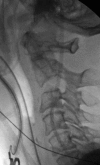

Fractures of the second cervical vertebra (C2, axis) are common in adult spine surgery. Those fractures occurring in younger adult patients are often associated with high-energy mechanism trauma, resulting in a "Hangman's Fracture." Management of these fractures is often successful with nonoperative means, though surgery may be needed in those fractures with greater displacement and injury to the C2-C3 disc. Older patients are more likely to sustain fractures of the odontoid process. The evidence supporting surgical management of these fractures is evolving, as there may be a mortality benefit to surgery. Regardless of treatment, longer-term mortality rates are high in this patient population, which should be discussed with the patient and family at the time of injury. Pediatric patients may suffer fractures of the axis, though differentiation of normal and pathologic findings is necessary and more difficult with the skeletally immature spine.